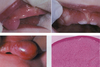

MEN 2B (Multiple Endocrine Neoplasia Type 2B)

Lymphangioma